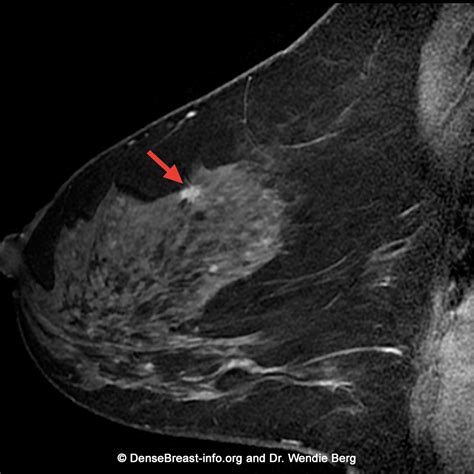

Breast MRI with dye, also known as contrast-enhanced breast MRI, is a powerful diagnostic tool used to detect and evaluate breast abnormalities. This advanced imaging technique provides detailed images of the breast tissue, helping healthcare professionals to identify and diagnose conditions such as breast cancer, fibrocystic changes, and other breast diseases. Unlike traditional mammography, which uses X-rays, breast MRI with dye utilizes magnetic fields and radio waves to produce high-resolution images. The contrast dye enhances the visibility of blood vessels and tissues, making it easier to detect abnormalities that might be missed with other imaging methods.

Breast MRI with dye is particularly useful for women who have dense breast tissue, a family history of breast cancer, or who are at high risk due to genetic mutations such as BRCA1 or BRCA2. The procedure involves injecting a contrast agent into the bloodstream, which helps to highlight areas of increased blood flow, a common characteristic of tumors. This enhanced visibility allows radiologists to better differentiate between benign and malignant lesions.

• High Sensitivity: Breast MRI with dye is highly sensitive in detecting breast cancer, especially in women with dense breast tissue. It can identify small tumors that may not be visible on mammograms.

• Detailed Imaging: The use of contrast dye enhances the visibility of blood vessels and tissues, providing detailed images that help radiologists differentiate between benign and malignant lesions.

• Early Detection: Breast MRI with dye can detect breast cancer at an early stage, when it is most treatable. Early detection significantly improves the chances of successful treatment and survival.